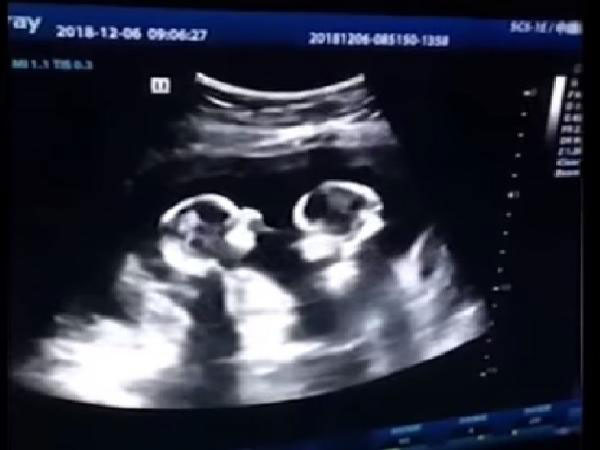

വീഡിയോ പുറത്ത് വന്നത് അവസാന വര്ഷമാണ്. ചൈനയിലാണ് സംഭവം. ഭാര്യയുടെ അള്ട്രാ സൗണ്ട് സ്കാനിംഗിലാണ് ഇത്തരത്തിലുള്ള ഒരു അപൂര്വ്വ കാഴ്ചയുണ്ടായത്. രണ്ട് പെണ്കുട്ടികളായ ഇരട്ടക്കുട്ടികളാണ് ഇവര്ക്ക് ജനിച്ചത്. നാല് മാസം മാത്രമായിരുന്നു ആ സമയത്ത് അവര് ഗര്ഭിണിയായിരുന്നത്.

അള്ട്രാ സൗണ്ട് സ്കാനിംഗില് കണ്ടത്

എന്നാല് പരസ്പരം വഴക്കടിക്കുന്ന ഗര്ഭസ്ഥശിശുക്കളെയാണ് ഇവിടെ സ്കാനിംഗില് ഡോക്ടര് കണ്ടത്. നിമിഷ നേരം കൊണ്ട് തന്നെ ഈ വീഡിയോ ലോകമെമ്പാടും വൈറലായി. കുട്ടികളുടെ അച്ഛന് തന്നെയാണ് ഇത്തരത്തിലുള്ള ഈ വീഡിയോ സോഷ്യല് മീഡിയയില് പങ്കു വെച്ചത്.